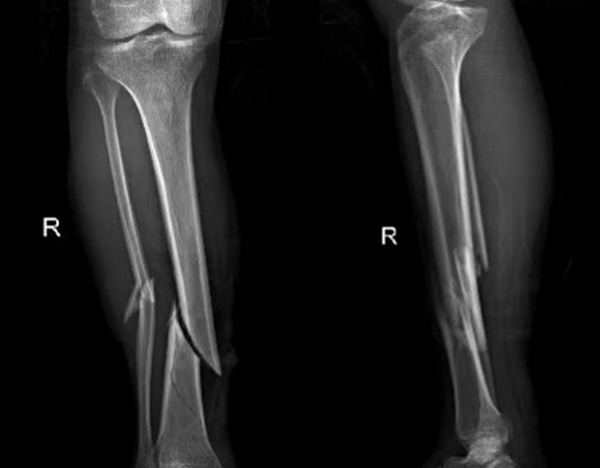

比如外傷患者,排查有無四肢骨折,X光片是首選,因?yàn)樗芸焖偾逦@示骨骼的連續(xù)性;而檢查關(guān)節(jié)內(nèi)的軟組織(如韌帶、半月板),則需要靠MRI,CT對(duì)此幾乎“無能為力”。所以,別主動(dòng)要求“升級(jí)”檢查,聽從醫(yī)生的專業(yè)建議,才能既準(zhǔn)確又高效。